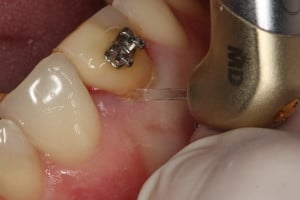

Przykład ekstruzji ortodontycznej za pomocą płytki termoformowalnej i zameczka ortodontycznego: